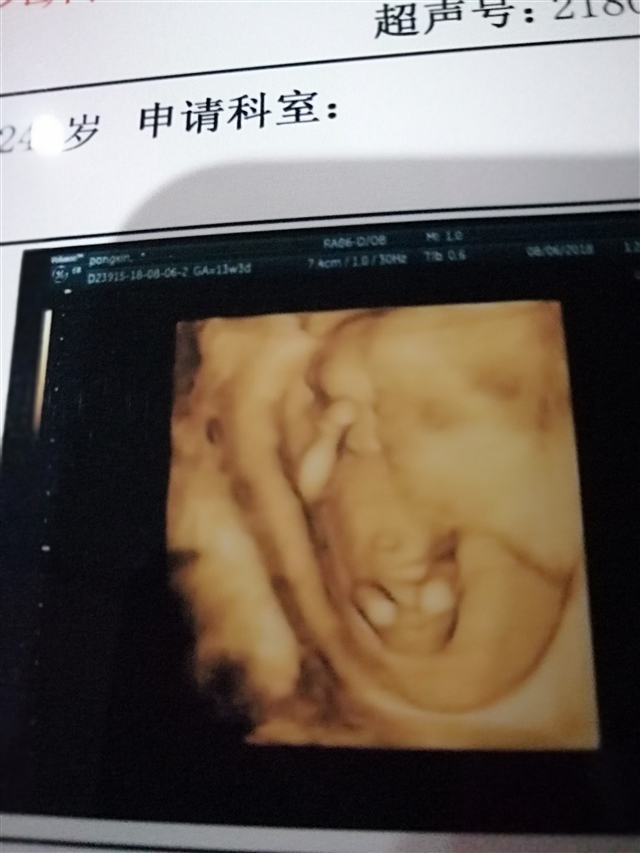

孕19周+1天

捂着眼睛呢……

普通人看不懂吧

欣心新鑫锌昕馨芯歆[帖主]:都看不懂

好像男的吧,看不太清楚

欣心新鑫锌昕馨芯歆[帖主]:我也看不清